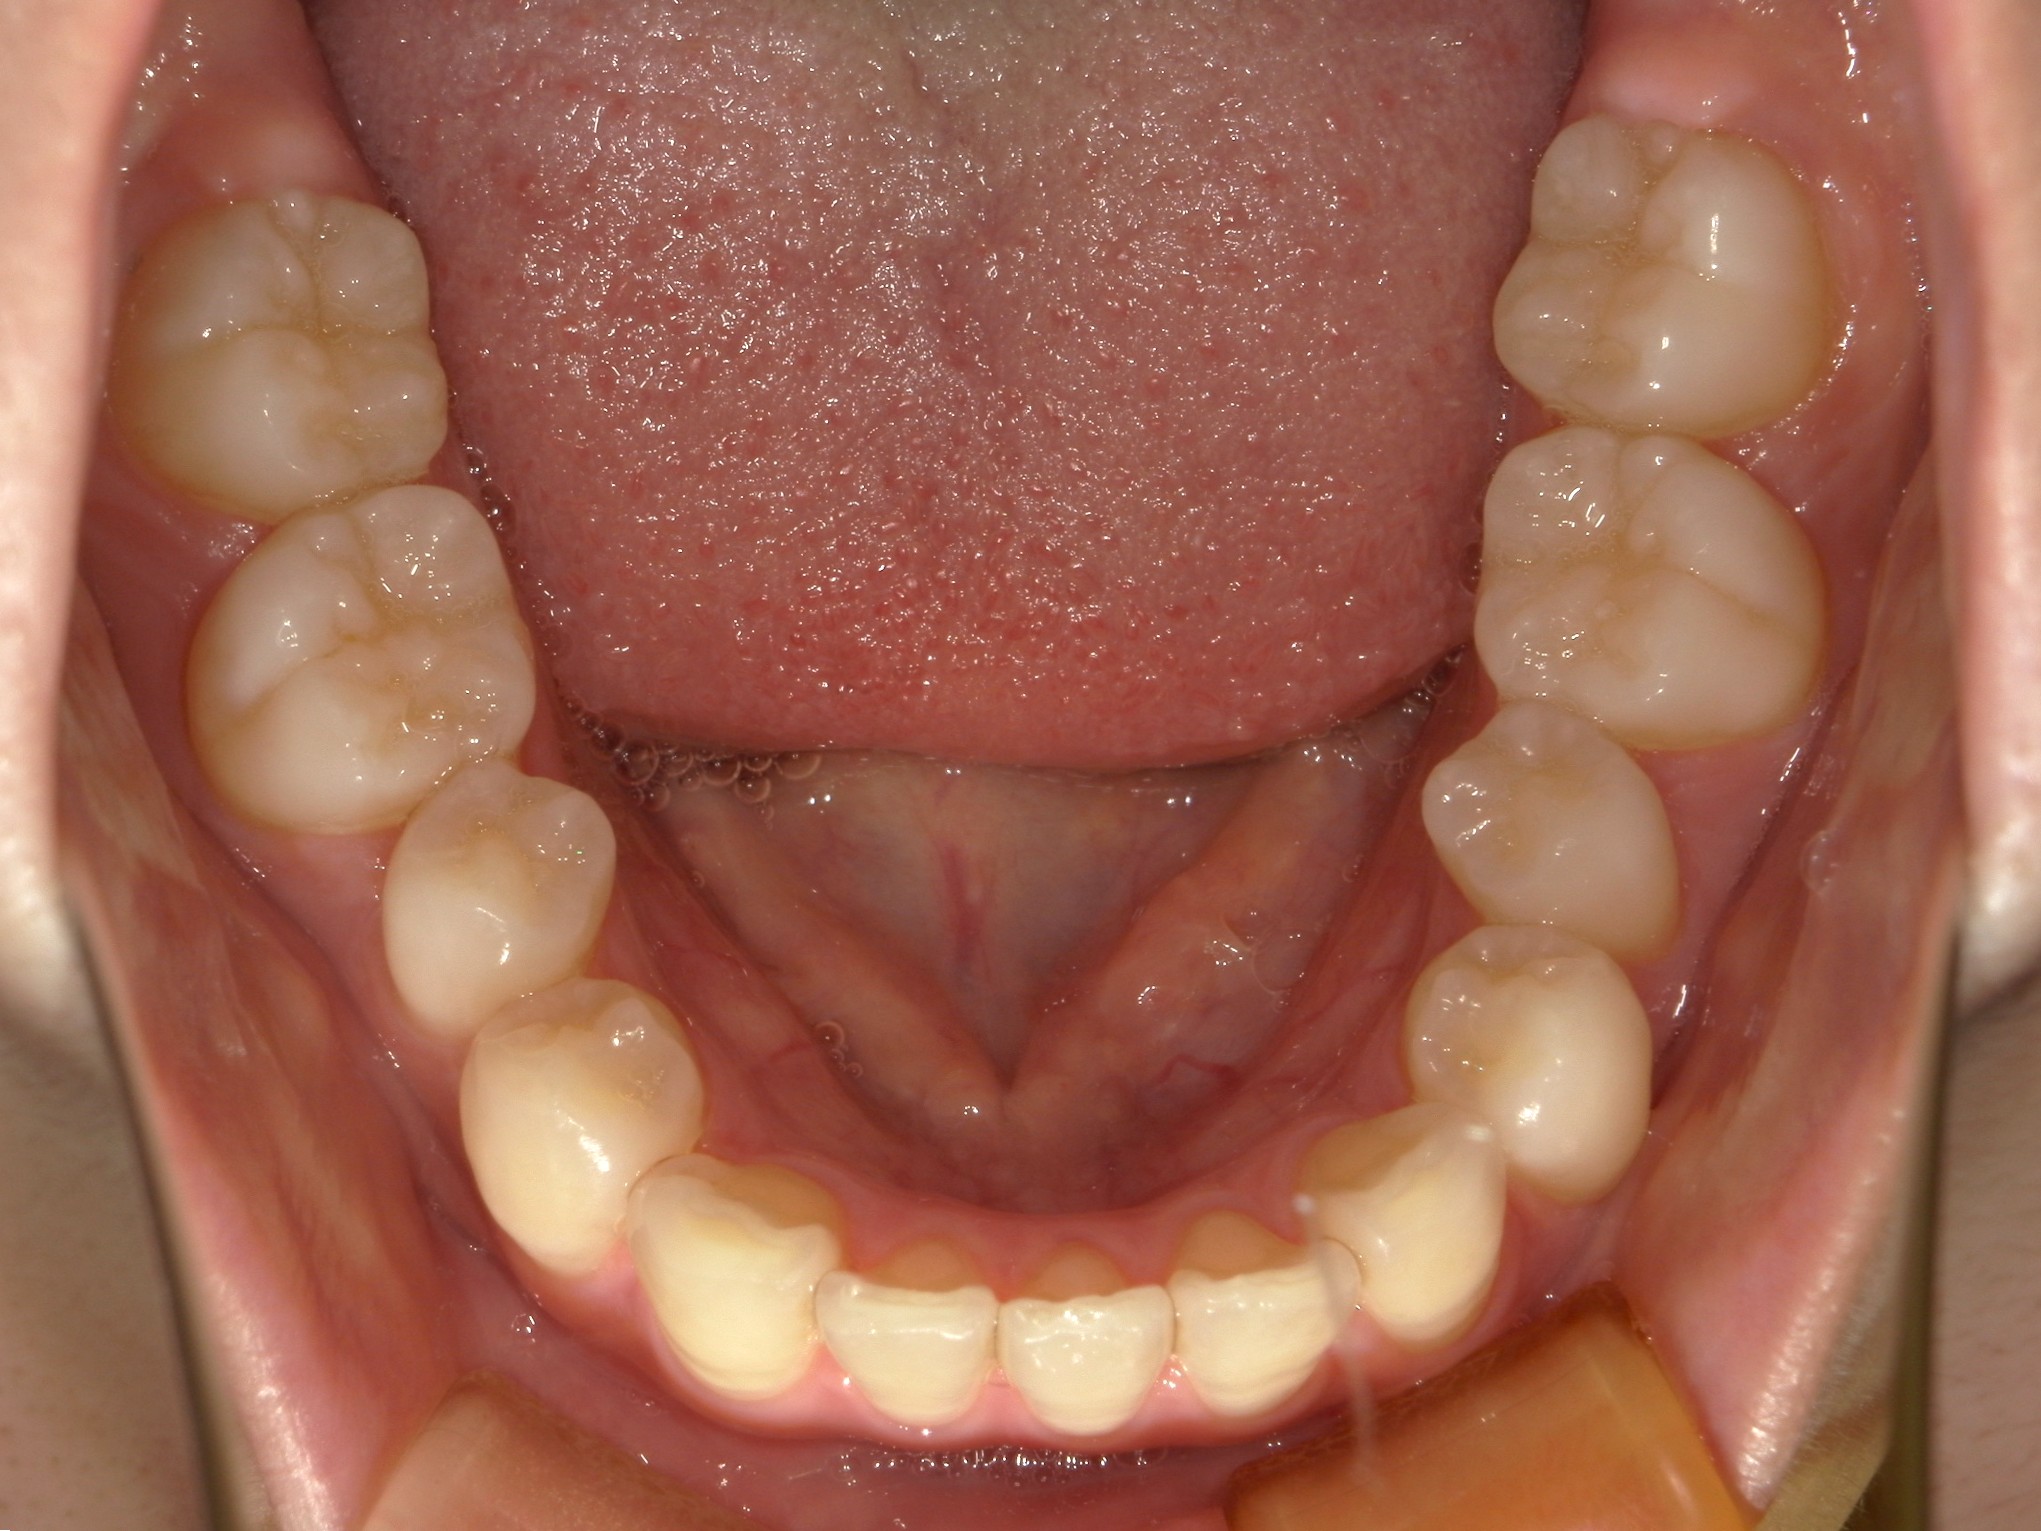

横から見た口腔内写真でよくわかるように、前歯が出っ歯になっており、全く咬んでいない状態でした。また下の前歯が本来4本あるところが、先天的に一本少なく3本しかない(Three incisors)であったため下顎のアーチが小さいというお口の状態でした。前歯を正しい傾きに治し、咬合させるため、上の歯のみ2本の抜歯を行うこととしました。下の前歯が3本のため、その正中に注意しながら前歯の傾きを修正し、奥歯のポジションを整えて仕上げました。口元の突出感は大きく改善し、咬合も良好な状態で完了することができました。

口内下

治療前

治療後